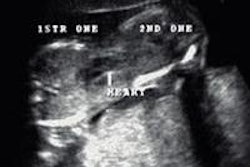

The guidelines outline in detail the various cardiac sources of embolism and imaging strategies for each, in harmony with previously published society guidelines. It also includes a dedicated section on cardiac sources of embolism in pediatric populations. The document contains more than 40 figures, nine tables, and 43 videos, which include imaging techniques, strategies for overall evaluation, reporting recommendations, and comparisons of echo modalities.